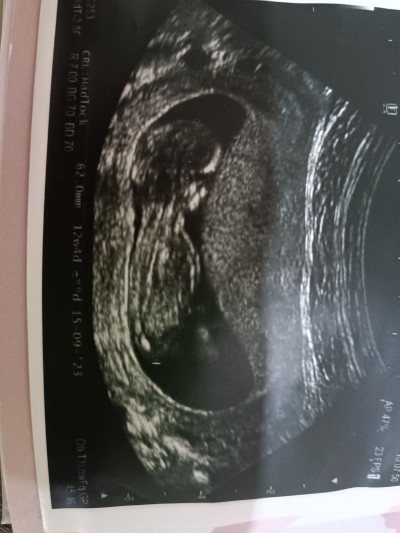

Cinsiyet tahmini resimli....

Doktor tahminde bulundu ama yinede merak ettim

Kesin erkek :)

Kesin olmamakla beraber erkeğe benzettim dedi :))

Kiz kiz kiz: D

Keseye göre tahmin ettim kız bebek bence ☺️

Bakar bakmaz erkek dedim